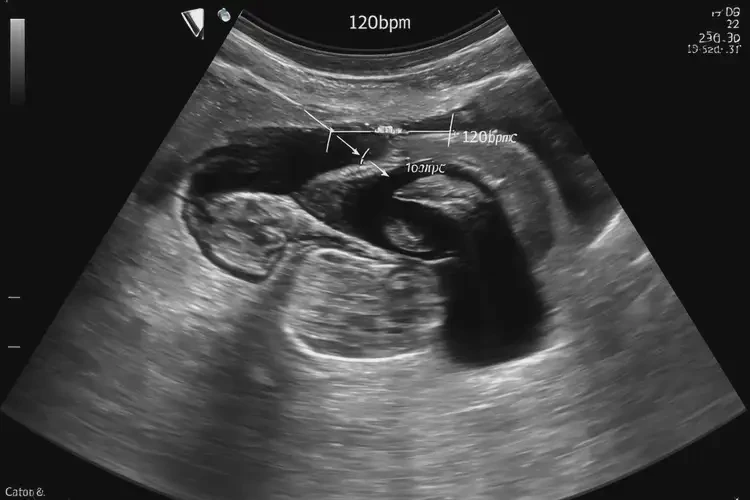

胎心98次/分鐘

在孕29周4天時,胎心率為98次/分鐘,這低于正常范圍。正常情況下,胎兒的心率應(yīng)在110-160次/分鐘之間。胎心率異??赡苡啥喾N原因引起,需要進(jìn)一步評估和監(jiān)測。

胎心率可以通過胎心監(jiān)護(hù)儀多普勒超聲進(jìn)行監(jiān)測。這些設(shè)備能夠?qū)崟r記錄胎兒的心跳,并提供有關(guān)胎兒健康狀況的信息。

孕29周4天胎心98怎么回事(圖1)